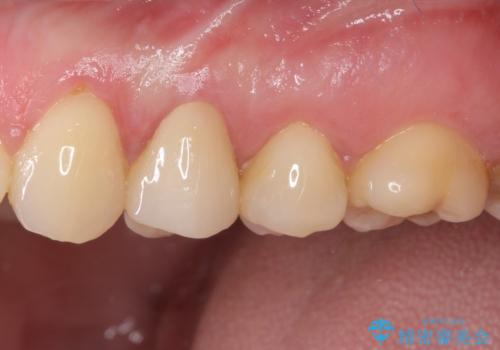

根管治療を行った奥歯は、再発防止や残された歯質を守るため、クラウンによる補綴治療が必要となります。

補綴後6ヶ月経過しレントゲンを撮影したところ、根尖周辺の病変が消失していることが確認できました。